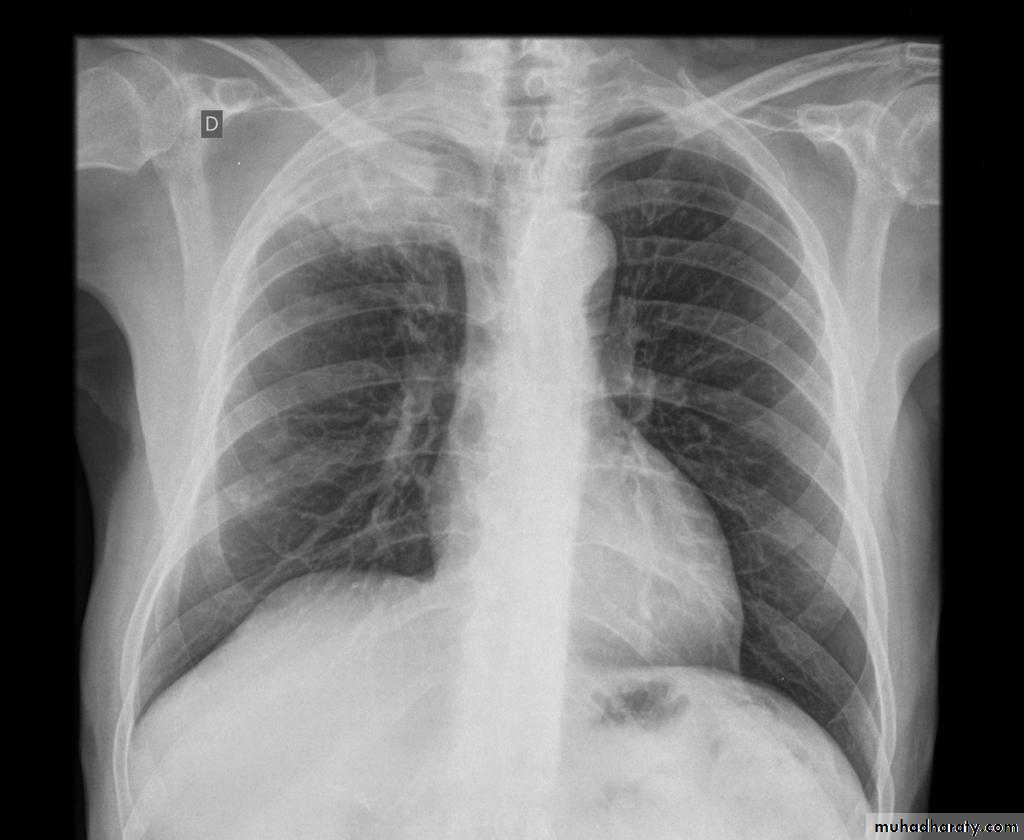

Right upper lobe consolidation

RUL consolidation will be seen as an increased opacity within the right upper lobe. Opacity may be sharply bordered by the horizontal fissureSome loss of outline of the upper right heart border may be apparent

Radiological sign in chest radiograph

Dense opacity seen above the horizontal fissure.

Air-bronchogram line

The lower border of the consolidation is sharply delinated by the horizontal fissure suggesting it lies in the anterior segment of the RUL